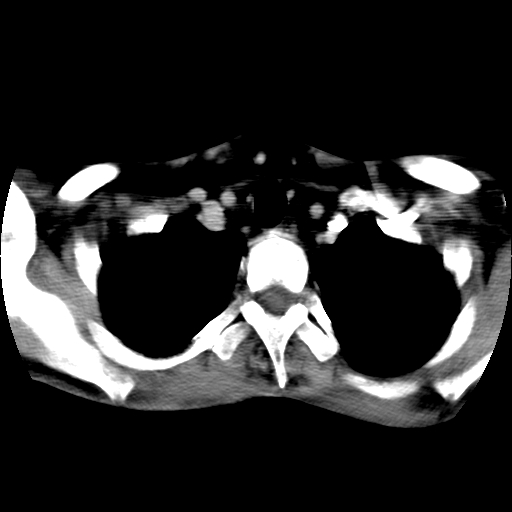

标题: CT24019:男,45岁,发现颈部肿物5个月。 [打印本页]

标题: CT24019:男,45岁,发现颈部肿物5个月。

男,45岁,发现颈部肿物5个月,彩超示:双侧颈部及下颌部软组织增厚。

考虑双侧颈项部良性对称性脂肪增多症。

双侧颈项部脂肪沉积